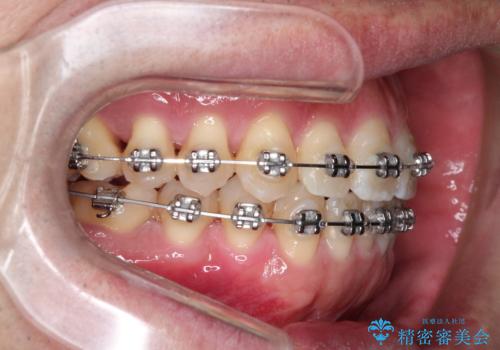

ワイヤーによる全体的ながたつきの矯正治療

- 30代男性

- メタル

- 1年3ヶ月

- 全体的ながたつきを治したいとのことで来院されました。

ワイヤー矯正とマウスピース矯正の二つの器具での治療をご案内し、ワイヤー矯正を選択されました。

インビザラインを装着するのがめんどうなので、ワイヤーの方があっているとのことで今回の治療方法を選択されました。